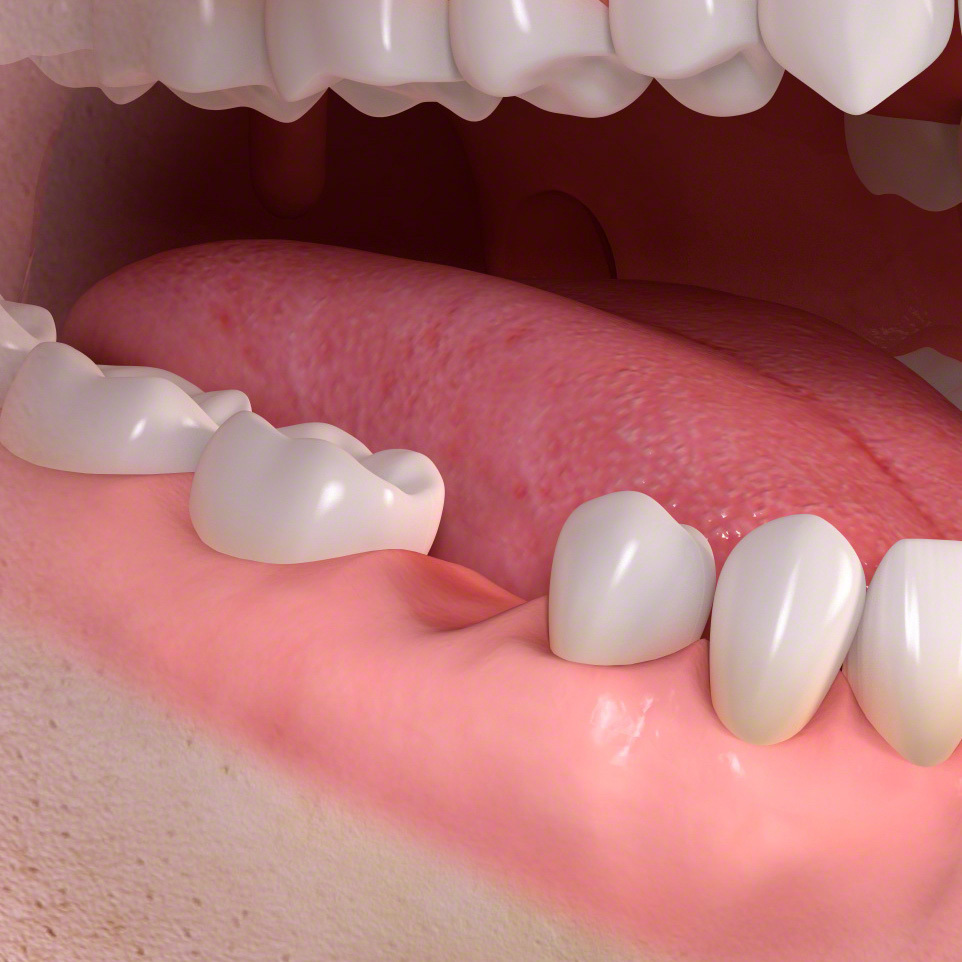

ブリッジ

・健康な歯であっても、土台にするために小さく歯を削る必要があります。

歯の欠損

ブリッジは少数の歯を失った時に行う治療法です。

前後の土台になる歯が平行に生えている場合のみ可能な治療法です。

ブリッジ準備

無い場所に歯を作るため前後の歯を平行に小さく削ります。

3本つながった歯の被せ物をセメントで固定します。

保険の場合、奥歯は銀歯になります。

白い歯をご希望の場合は自費のセラミックになります。